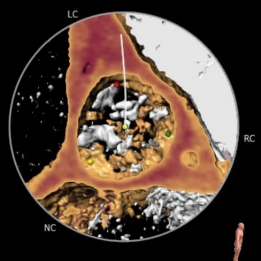

术前CT结果显示,患者主动脉瓣瓣环周长:82mm ,平均瓣环直径:26.1mm,左流出道平均直径27.0mm,瓦氏窦最小径32.5mm,窦管结合交界处(STJ)31.1mm,三叶瓣,中度钙化,钙化分布不均匀,主要位于无冠窦,瓣叶未见增生肥厚。左冠高度尚14.5,右冠高度9.9,可见右冠高度略低,结合瓣叶长度,瓣叶钙化分布等综合因素考虑,术中存在一定的冠脉遮挡风险。双侧入路血管直径尚可,无明显钙化,最小直径为8.9mm。

主动脉根部评估

冠脉阻挡风险评估及钙化程度分析